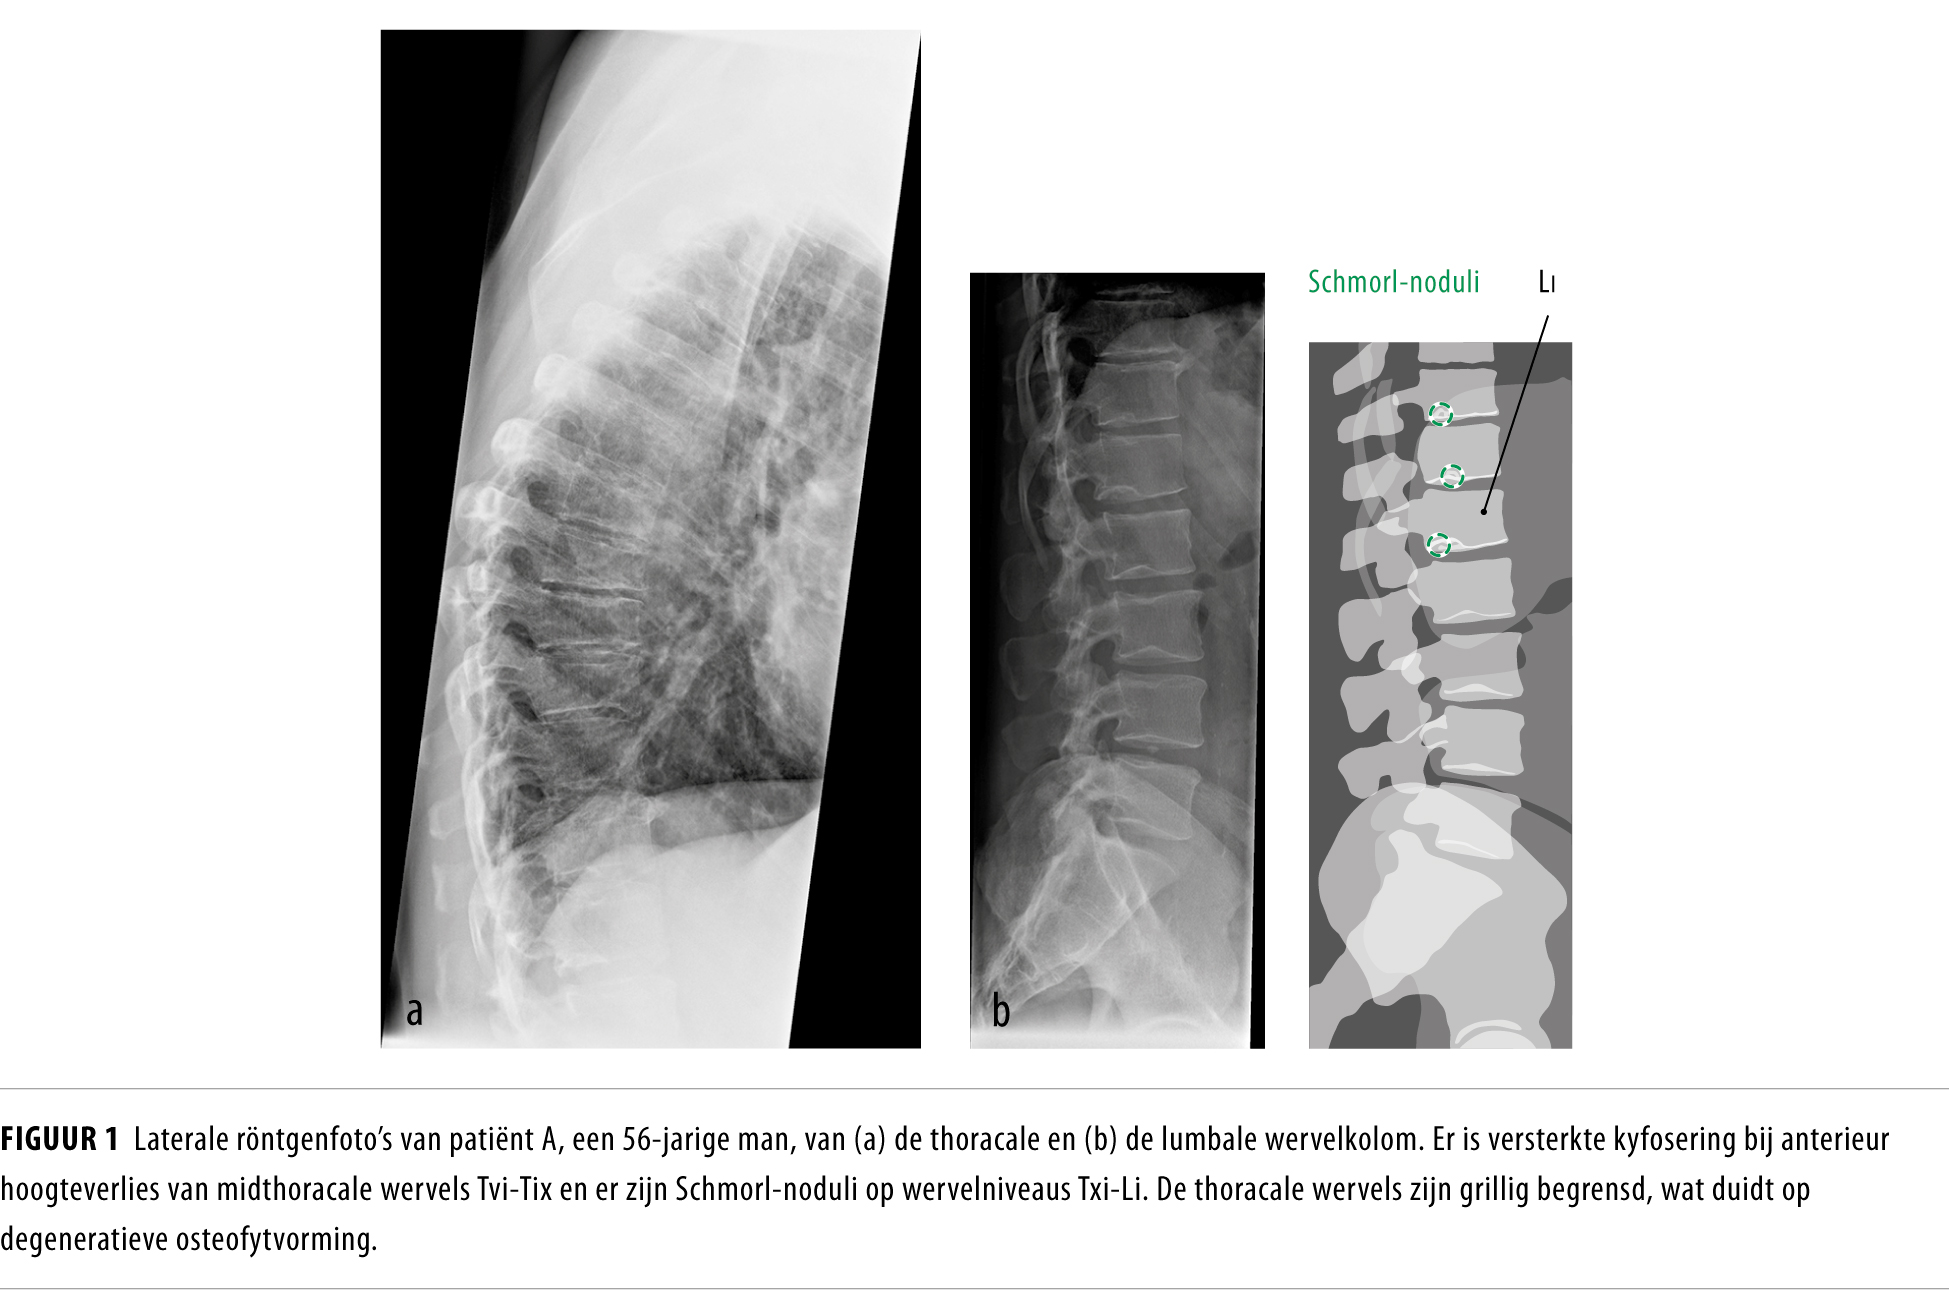

Osteoporotische wervelfracturen of ziekte van Scheuermann? NTvG